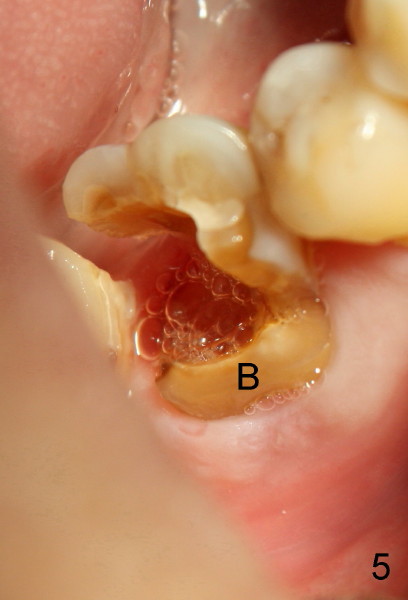

On the second appointment, the buccal wall is fractured (Fig.5: B). Visibility improves. Straight access is obtained, particularly mesially, but DL orifice is still not found. So D canal appears to be the only canal distally. It is further debrided with 40/.04 file. PA is taken when master cones are inserted (Fig.6). This time DL root is quite obvious.